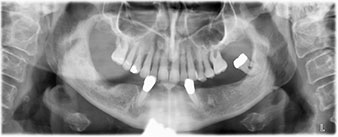

The 64-year-old patient presented with residual dentition of teeth 38, 33 and 43 and a clasp denture in the mandible (Fig. 1 and 2).

residual dentition

Fig. 1

Fig. 2

A three-dimensional cone beam computed tomography scan (CBCT, Planmeca) was performed to aid planning and minimize risks. This revealed that the quality and quantity of the available bone were sufficient for the surgery and immediate restoration using the Fast & Fixed method. Following the protocol for this concept, the implants are inserted at 35, 32, 42 and 45. Angling the distal implants by up to 45° shifts the emergence profile to posterior and generates a larger support polygon (Fig. 3).

Fast & Fixed method

Fig. 3